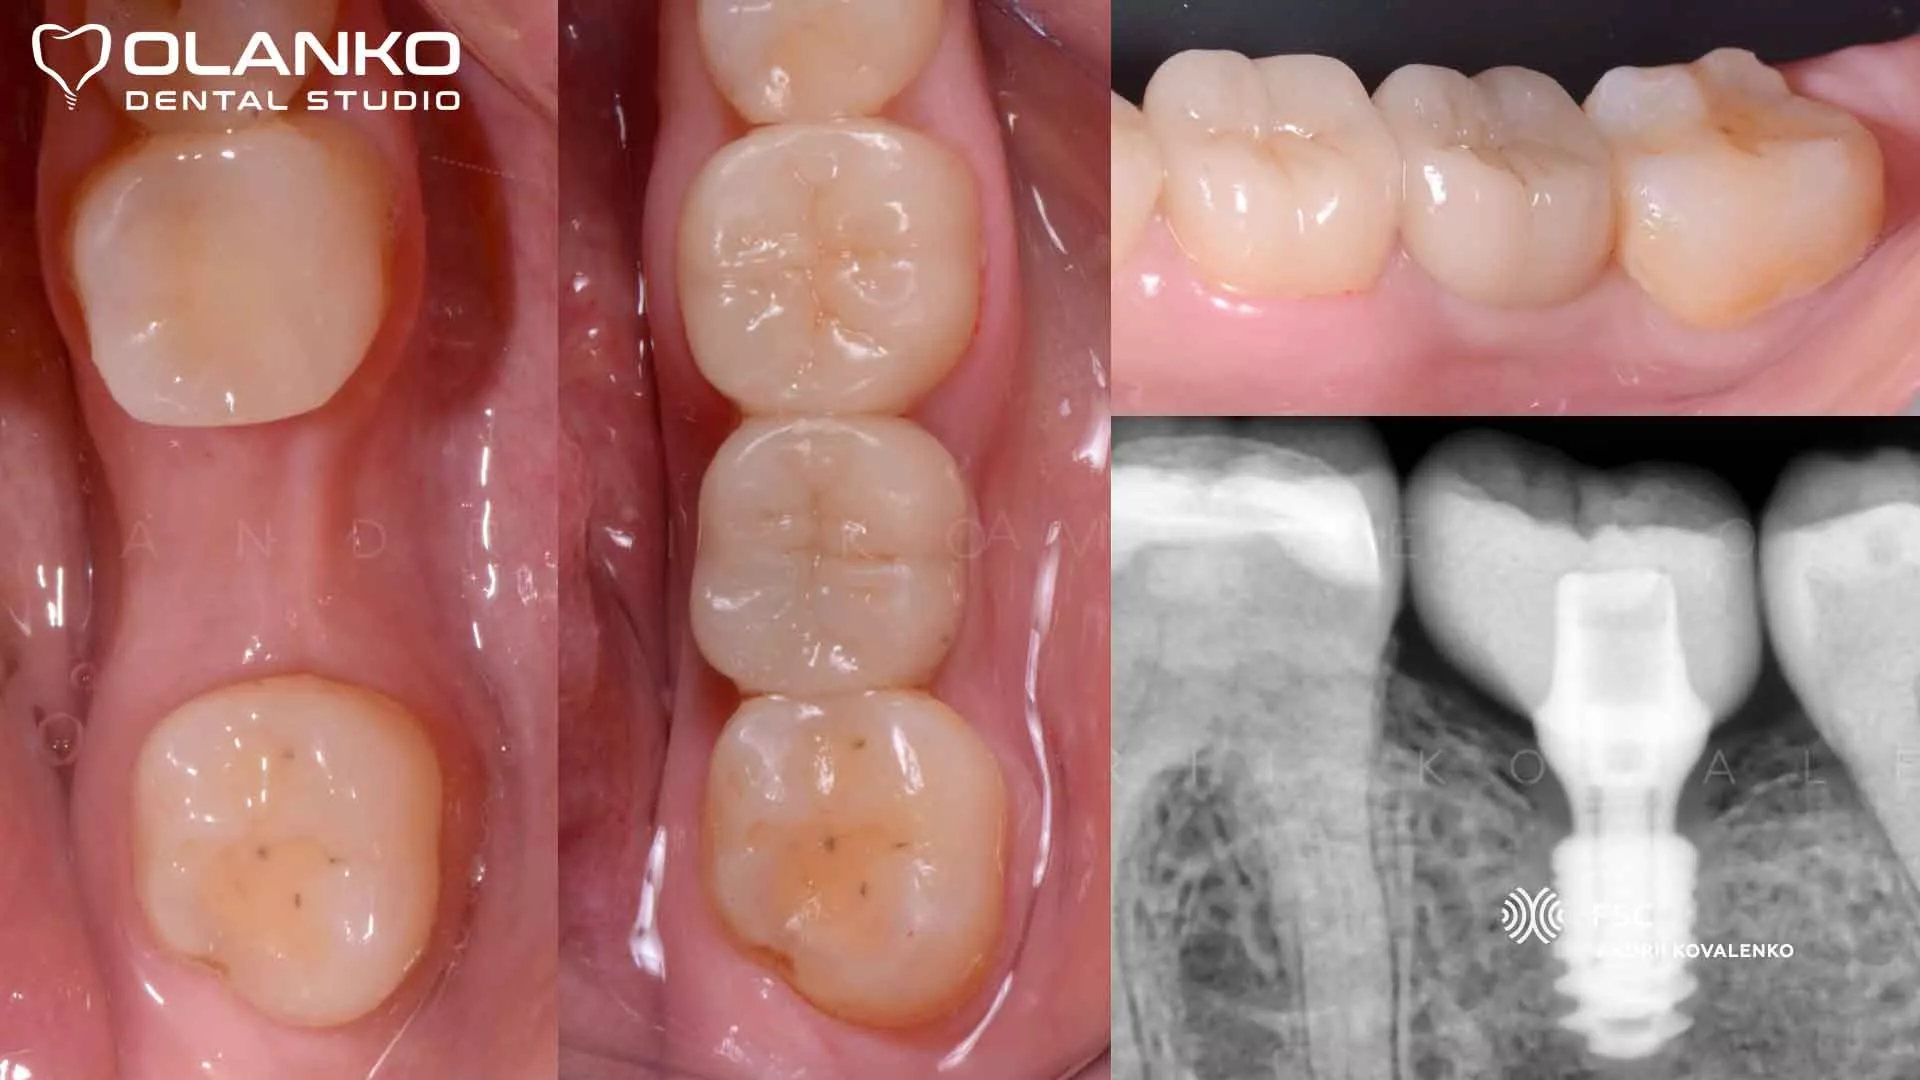

Мостовидный протез или имплант что лучше?

Мост или зубной имплант: что лучше выбрать?

В жизни многих людей встречаются ситуации, когда происходит потеря зубов. Отсутствие зубов во рту не только портит эстетический внешний вид улыбки, но и доставляет большой дискомфорт пациенту. Чтобы вернуть привлекательную улыбку, а также восстановить жевательные функции челюсти, можно обратиться к процессам протезирования. Современные стоматологические методы позволяют осуществить различные варианты протезирования зубов с учетом пожеланий клиента. Однако многие люди не могут решить что лучше выбрать: зубной мост или имплант.

Попробуем разобраться в характеристиках каждого метода и понять их "плюсы" и "минусы". Установление протеза мостовидного типа. Мостовидные протезы получили своё название из-за того, что они имеют особенную фиксацию, которая похожа на мост. Они закрепляются на собственных зубах пациента и при этом позволяют разместить необходимое количество зубов на том месте, где они были потеряны.

Мост представляет из себя цельную конструкцию, которая может восстановить улыбку. В настоящее время можно выбрать мостовидный протез из различных медицинских материалов, которые покрываются керамикой.

Установка имплантов, как процесс протезирования зубов.

Имплантанты - это наиболее современный и надежный метод для того, чтобы заменить потерянные зубы.

Имплантант включает в себя три основных элемента, а именно коронку, абатмент и искусственный корень. Имплантация показана в следующих случаях:

1. В том случае, если пациент не хочет совершать обточку зубов. По сравнению с мостовидными протезами имплантанты являются более современным, а также безопасным способом восстановить потерянные элементы.

Самым большим недостатком такого метода протезирования является то, что они дороже, чем протезирование мостовидного типа.